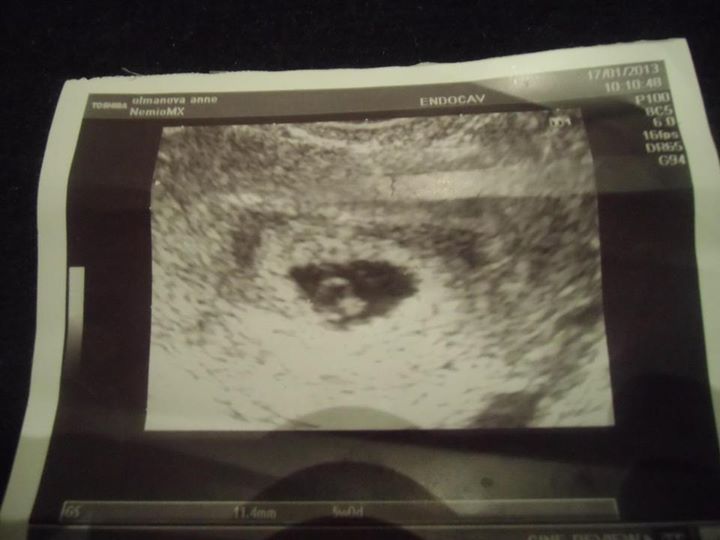

Jak Nelinka přišla na svět

První termín 20.5.2013 nevyšel. Ten termín, ve který jsem tolik doufala – byla jsem přesvědčená, že malá byla počata dřív, doktor mě neustále strašil velkou porodní váhou a já se upínala k tomu, že malá vyleze na tento termín.

Nakonec se ukázala její dochvilnost a podívala se na svět v den druhého termínu 26.5.2013. Ten den ráno jsem se vzbudila jako více méně každý den – bez příznaků, zcela ok. Verdikt z poslední kontroly u dr. Byl – otevřená volně na prst, cs 2. Říkám si v duchu – Neli – dnes ti končí nájemní smlouva, víš o tom celých 9 měsíců – tak co bude? Den probíhal normálně, po obědě manžel upekl koláč a kolem 16 hod. jsme zasedli ke stolu a začali si na něm pochutávat. Koukám na hodiny a říkám mu –noo, má ta naše Nelinka co dělat, bude půl páté – jestli má být do půlnoci venku – a manžel – no já jí čekám až někdy v týdnu. Potom jsem šla uklidit nádobí a najednou MOKRO! Říkám, ono to teče! Co??? Asi voda – plodová! J a můj zběsilý úprk na WC. Říkám – dones vložku! Chudák muž pobíhal jak splašený a nemohl ji najít. Uf, vložka nelezena, umístěna. Říkám, počkáme – nebylo toho zase tolik. Návrat do kuchyně a najednou – LUP- a teklo to mooc! Tak a pojedem J dobalila jsem tašku, napsala jsem vám na koníka a vyjeli jsme. Po cestě, která nám trvá cca 45 min začaly kontrakce po 8 minutách. Já nadšená, jak se nám to rozjíždí, zatím to moc nebolelo, žertovali jsme, jak je malá přesná J